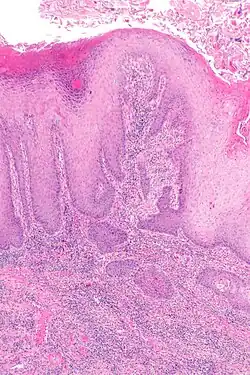

![]() Rak płaskonabłonkowy (kolczystokomórkowy) prącia | |

Rak prącia – nowotwór złośliwy wywodzący się z nabłonka prącia, najczęściej z żołędzi lub napletka. Występuje najczęściej w starszym wieku. W Polsce zapadalność na ten nowotwór wynosi 8 na 1 000 000 mężczyzn. Rak ten jest przyczyną 0,4% zgonów z powodu chorób nowotworowych. Najczęstszy typ rak prącia to rak płaskonabłonkowy. Z reguły przyjmuje postać wrzodziejącą, choć występuje również pod postacią naciekającą lub brodawkowatej narośli. Rzadziej występują inne nowotwory złośliwe: czerniak, mięsak, rak podstawnokomórkowy.